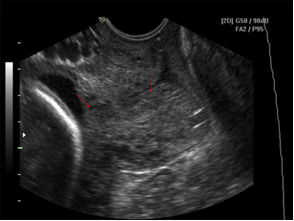

Đoạn dưới tử cung co làm lỗ trong CTC bị che khuất => sai lệch: kênh CTC đo dài hơn bình thường (hình 6.8)

Hình 6.8. Kênh CTC bị đo dài hơn bình thường